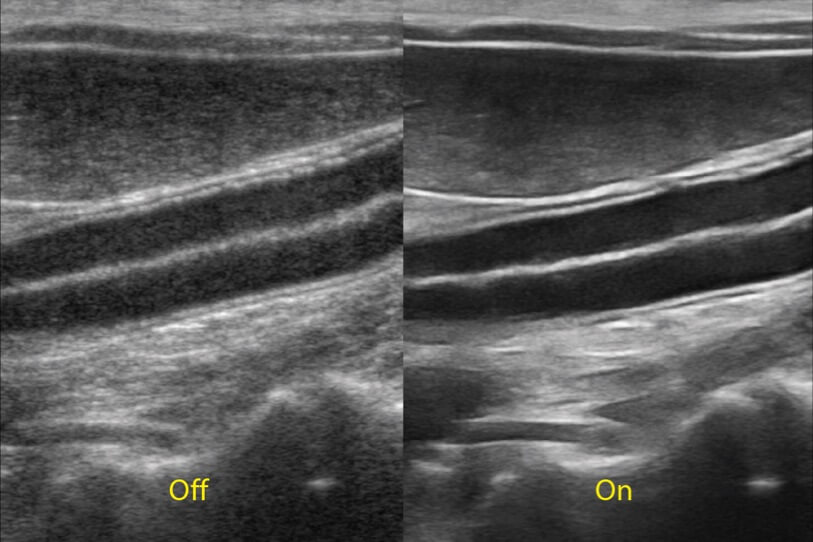

ProPet 70 進(jìn)一步提升了微米成像算法,更加注重對基礎(chǔ)原始圖像的還原和保留,在有效減少斑點(diǎn)噪聲、增強(qiáng)組織邊界顯示的同時(shí),避免過度優(yōu)化丟失真實(shí)的解剖信息。